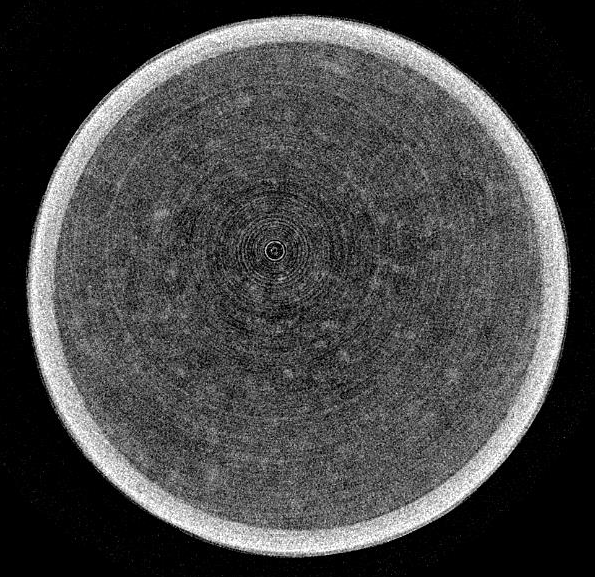

リングアーチファクト